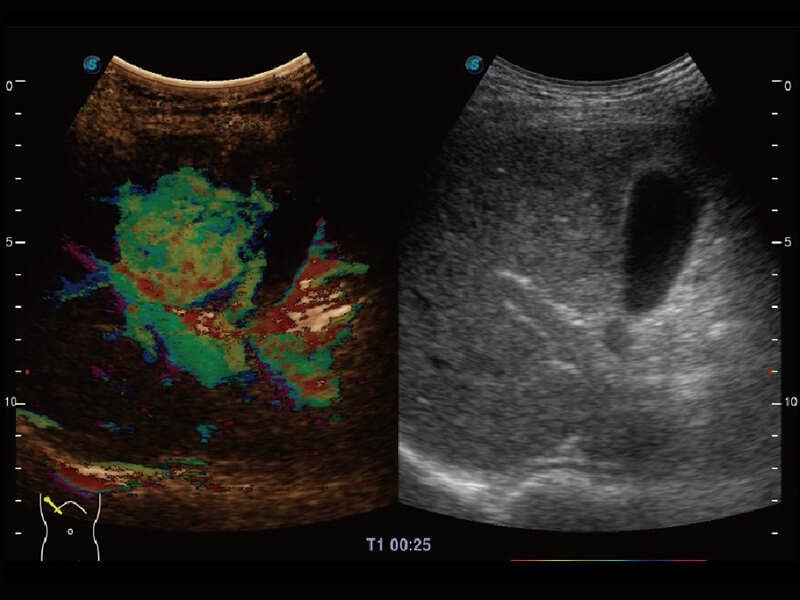

Micro F 显微血流成像 明察秋毫

临床图